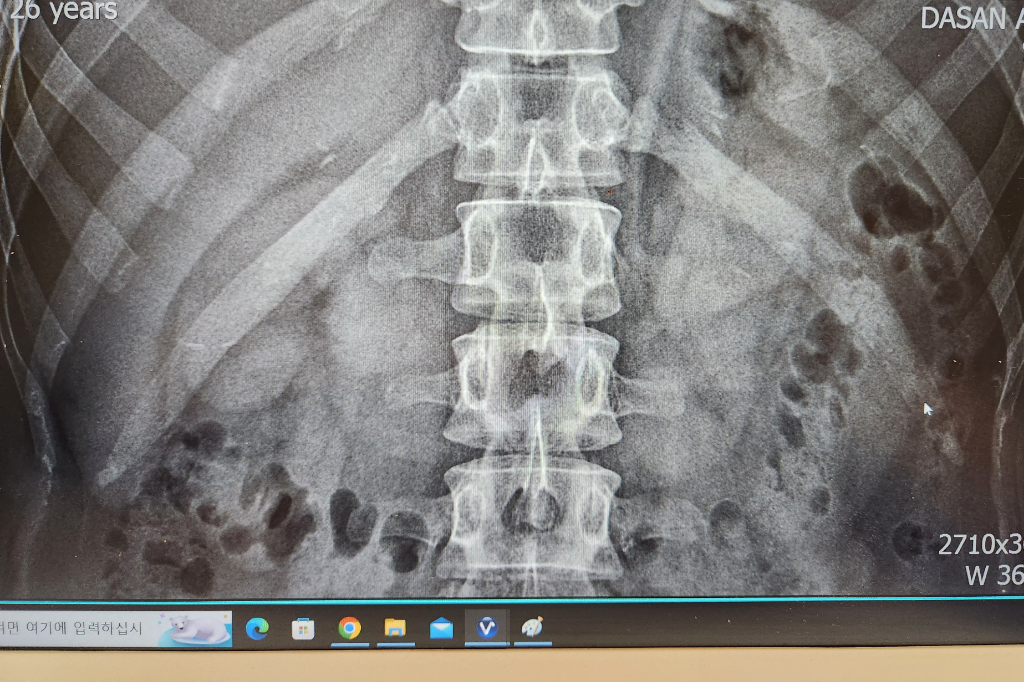

사진의 소견을 통해서 보았을 때에 좌측의 12번 갈비뼈의 골절이 굉장히 의심스런 선이 보입니다. 해당 부위의 증상이나 엑스레이 소견으로 볼 때에 충분히 골절이라고 볼 수 있습니다. 한방은 전문성이 떨어지기 때문에 흉부외과적으로 진료를 보시는 쪽을 더 권고드립니다. 다만 갈비뼈 골절에 대해서는 스스로 붙을 때까지 추가적인 손상을 예방하고 환부를 쉬어주는 것이 최선의 치료법이기 때문에 병원에 가신다고 하여 특별한 것이 있지는 않을 것이며 진통제를 복용하며 경과를 지켜보는 것이 현재로서는 적절한 치료법입니다.

X-ray 로 봤을 때에도 왼쪽 12번째 갈비뼈 골절의 가능성이 있는데 현재 보이는

부분은 앞쪽 갈비뼈가 아닌 등쪽 갈비뼈에 해당됩니다. 등에 통증이 있고 그 부분에서